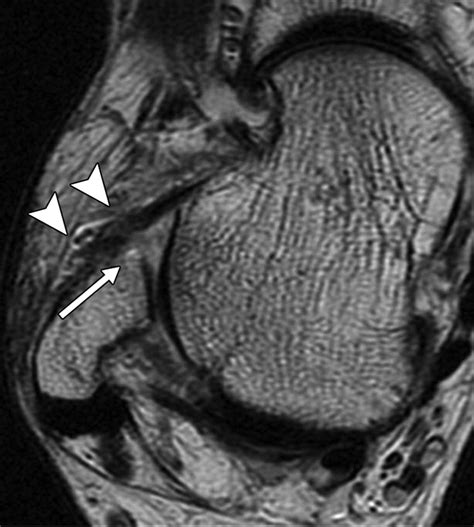

• Imaging Tests: X-rays can rule out fractures, while MRI or ultrasound can provide detailed images of the ligament to confirm the tear.